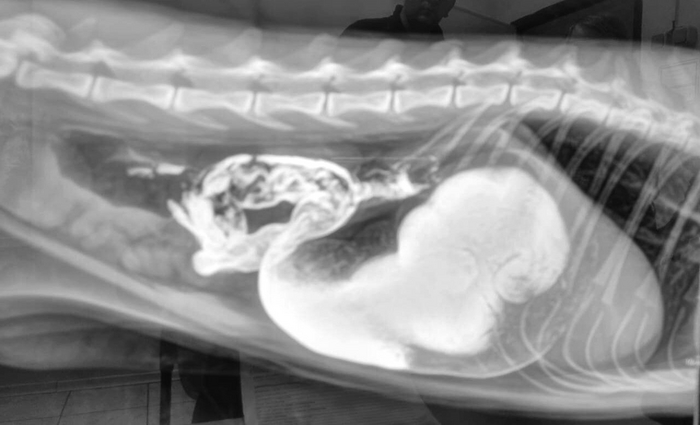

Московские ветеринары спасли полуторагодовалого мейн-куна Ватсона, который проглотил часть детского развивающего пробкового коврика.

Врачи, увидев инородный предмет на рентгене, не сразу поняли, что это: "Он напоминал кусок пробки от шампанского: неужели кот "хранил" это в себе с давно прошедших новогодних праздников? После успешного хирургического вмешательства Ватсон быстро пошёл на поправку, а владельцам вскоре удалось разгадать тайну "пробки"

Теперь коврик спрятали от питомца, сообщили в сети ветклиник "Мосветобъединение".